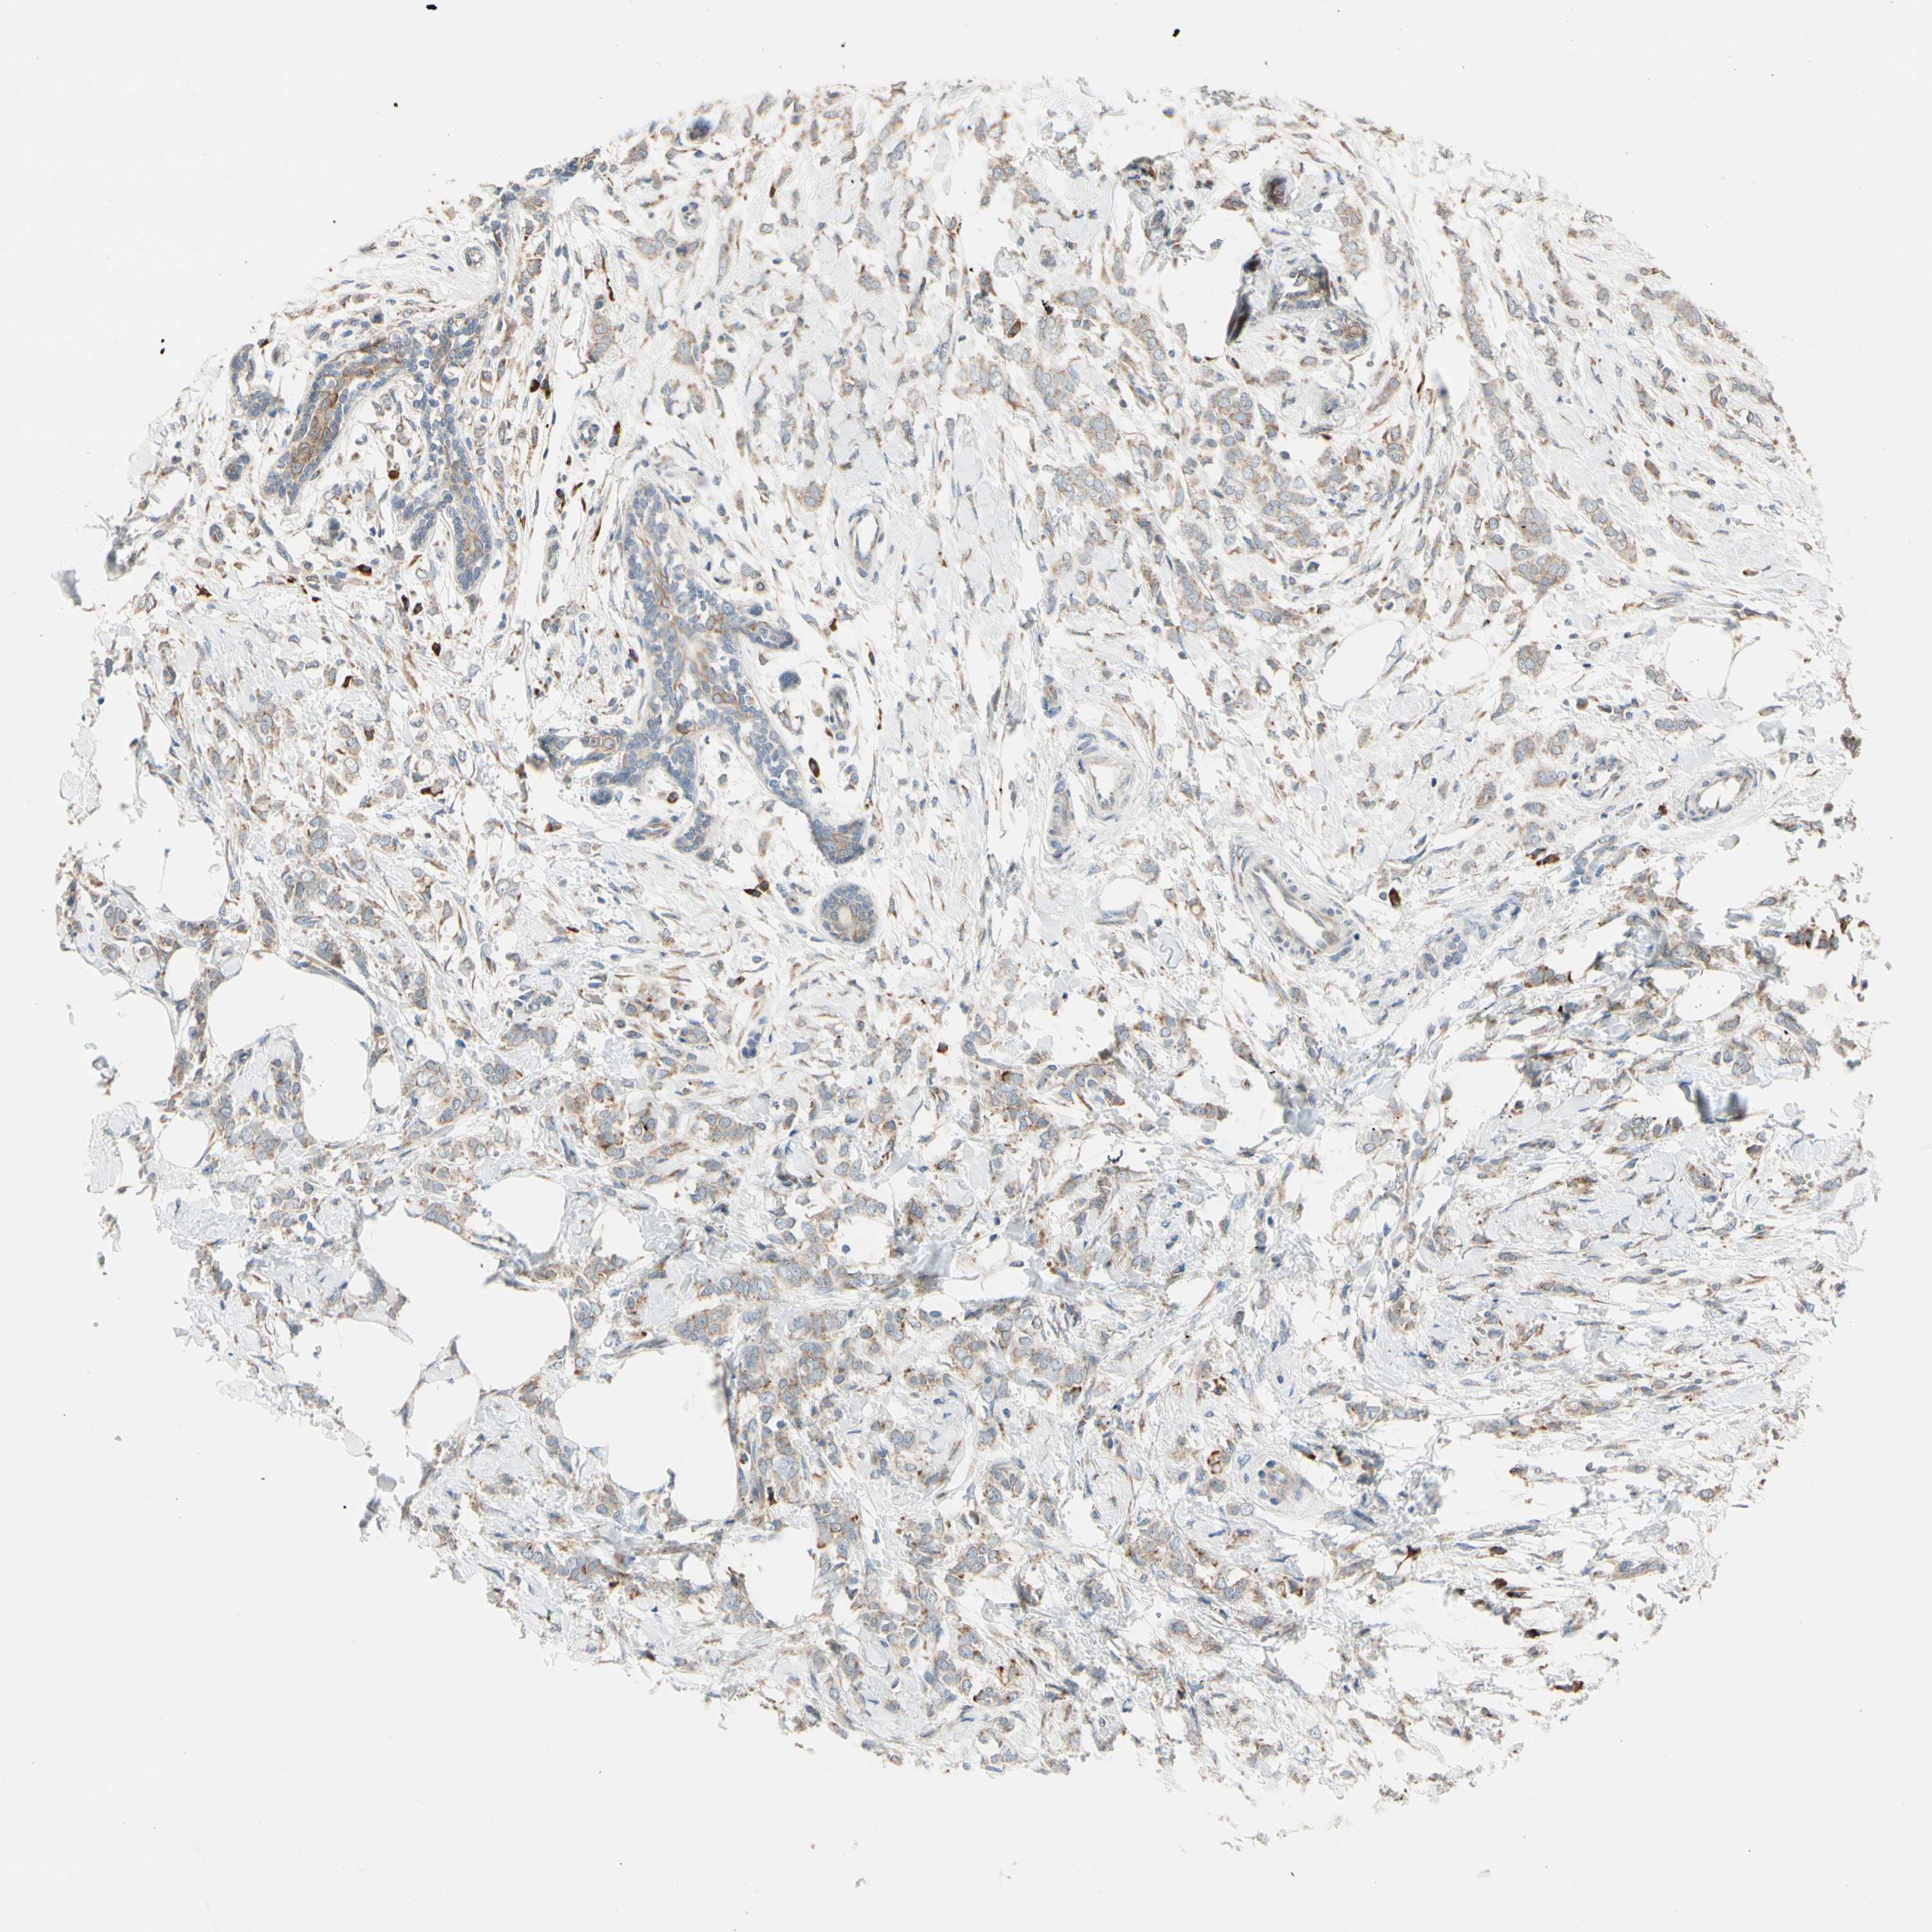

BRCA TCGA BRCA VALIDATION PROTEIN EXPRESSION

ANTIBODIES

AND

VALIDATION